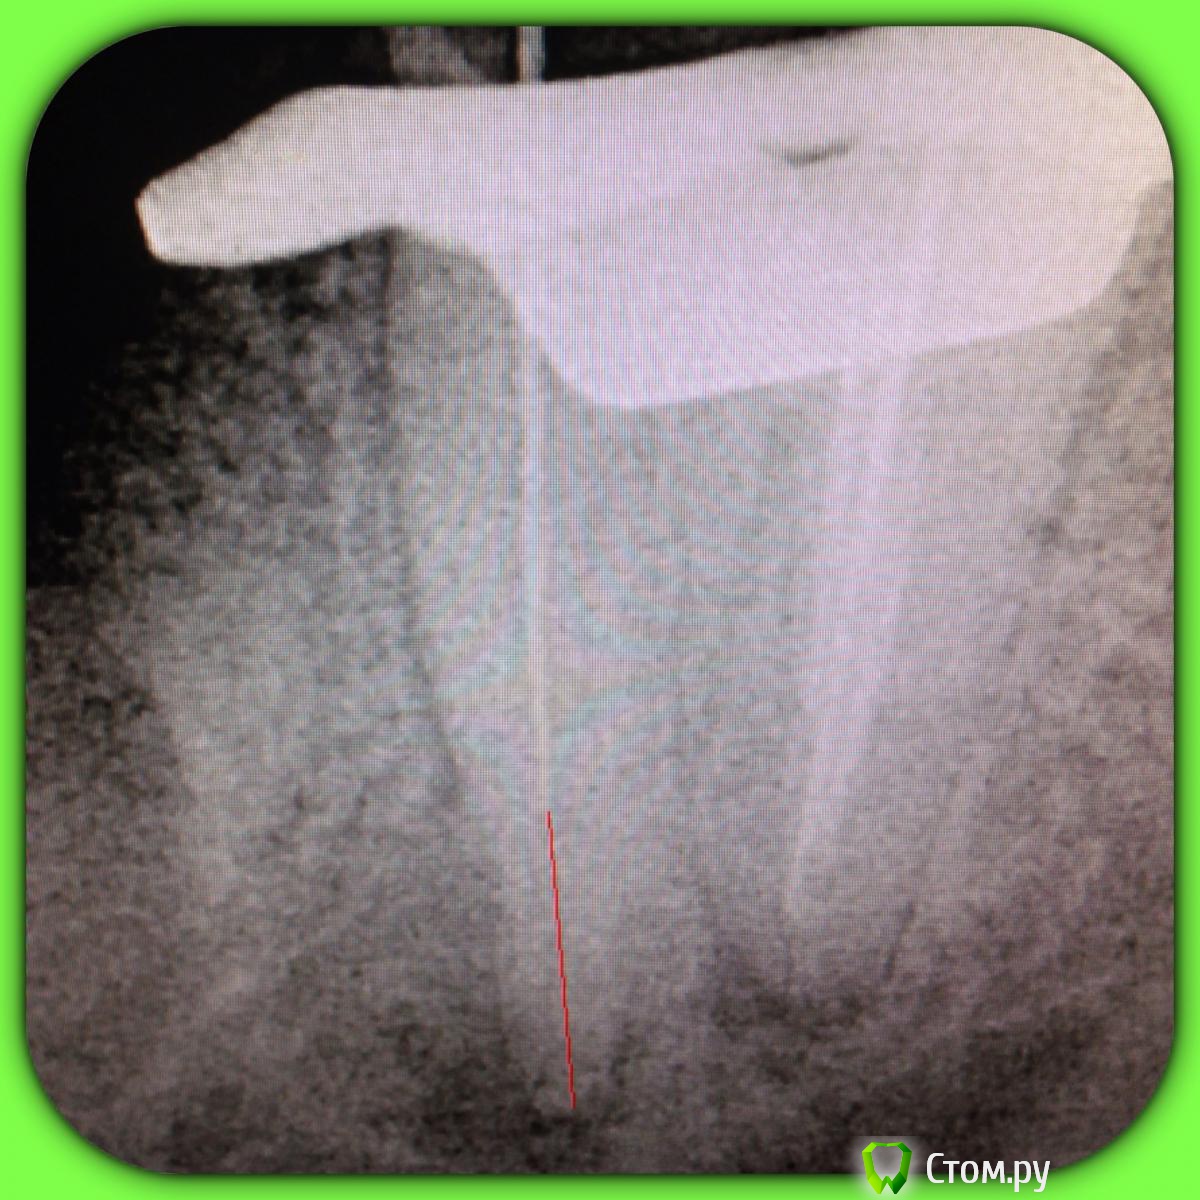

SSTi Опубликовано 13 июня, 2014 Автор Поделиться Опубликовано 13 июня, 2014 37. Медиальная стенка разрушена. Огромная старая пломба. Из жалоб только иногда болезненность по переходной. Редко. Очень. Делаю снимок. Коффер, преп, в дистальном какая-то паста плотная очень, светло-молочного цвета. В медиальный язычный без проблем попал. Щечный пришлось ковырять. Теперь о неприятном. Дистальный распломбировал, прошел, при этом раскрутил 3 протейпера и 1 профайл. В язычном медиальном проблем не было. А вот щечный- жутко узкий, прошел до куда смог. Раскрутил 3 протейпера, 2 профайла, 1 pathfile.... Дальше никак. До апекса еще миллиметров 5 точно. Хорошо хоть без поломок. Ручные к файлы гнулись только так. Даже десятка не идет. В общем очень хорошо помыл и кальций. Не знаю , что с щечным делать??? Биться дальше?? Сомневаюсь, что смогу. Это в процессе. Вот до куда дошел в щечном. С дистального потом убрал со стенок остатки материала Ссылка на комментарий

SSTi Опубликовано 13 июня, 2014 Автор Поделиться Опубликовано 13 июня, 2014 У язычного длина 23.5. В щечный файл заходит на 17-18мм. Надо будет развернуть трубку и сделать под углом в следующий раз. Апекс молчит как партизан в щечном. Ссылка на комментарий

SSTi Опубликовано 18 июня, 2014 Автор Поделиться Опубликовано 18 июня, 2014 Вот что вышло. Пробился до куда смог. Вымыл все очень интенсивно и долго. И запломбировал. Зуб после прошлого визита не болел Ссылка на комментарий

SSTi Опубликовано 18 июня, 2014 Автор Поделиться Опубликовано 18 июня, 2014 Я не считаю это успехом. Щечный пробил конкчно немного, но не до апекса. Зуб под наблюдение...Но думаю лучше так, чем перфо или сломать файл Ссылка на комментарий